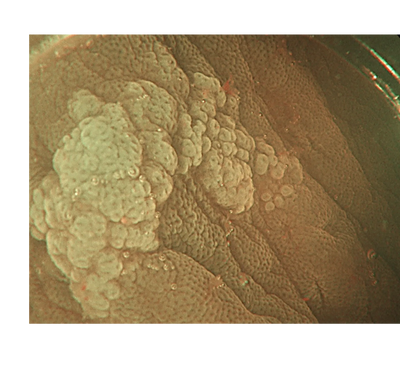

Rectal adenoma recurrence beneath a retained over-the-scope clip after previous EMR complicated by significant bleeding.

During follow-up, adenomatous tissue was identified growing under the OTSC. Attempted clip removal with an OTSC cutter was unsuccessful. The case highlights the role of endoscopic intermuscular dissection (EID) as a salvage strategy, which was successfully performed to achieve complete resection.